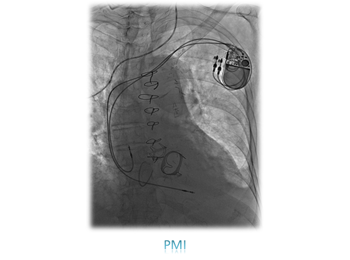

心臓カテーテル検査・治療

心臓カテーテル検査は、冠動脈や心腔内の描出および心臓内圧(心内血行動態)の情報などを得るために、カテーテルを動脈や静脈に挿入し、心臓まで到達させて行う検査で、主に検査(診断)と治療にわかれています。

検査には採取した血液中の酸素濃度を測定する検査、心臓の循環血液量を測定して機能情報を得る検査、造影剤を使って心臓の冠動脈の形態および壁運動を知る造影検査(CAGおよびLVG)などがあります。また不整脈の診断には、心臓内の電気の伝わる速さを調べる電気生理的検査(ESP)を行います。

一方治療には、狭くなった冠動脈にステントを留置する冠動脈ステント留置術(PCI)をはじめ、心臓以外の動脈や静脈を拡張させる血管拡張術(PTA)、頻脈性不整脈の原因となる電気回路を遮断させるため、心筋に高周波電流を流して焼灼するアブレーションや、徐脈性不整脈に対するペースメーカー埋込術(PMI)、除細動器のデバイス埋め込み術(ICD)などがあります。